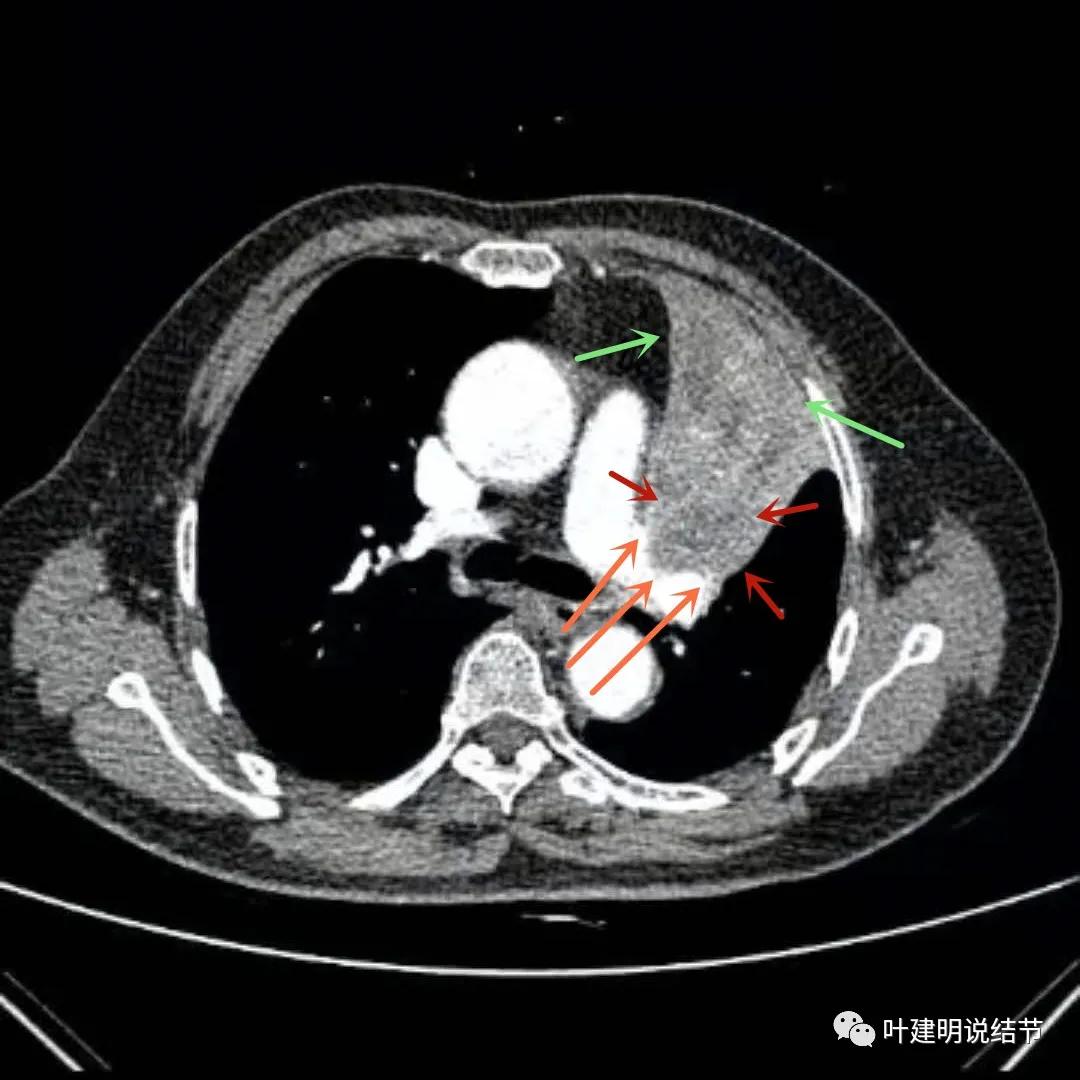

上图绿色箭头所指区域考虑不张的肺组织,红色箭头所指附近为肿瘤,且有膨胀性

上图绿色箭头所指区域考虑为肺不张,红色示肿瘤处,桔色箭头所指处是被肿瘤包绕的肺动脉分支

上图绿色箭头所指区域考虑为肺不张,红色示肿瘤处且有不均质与膨胀性,桔色细箭头所指处是被肿瘤包绕的肺动脉分支起始部,粗桔色箭头示肺动脉与肿瘤间紧密愈着,考虑有侵犯肺动脉